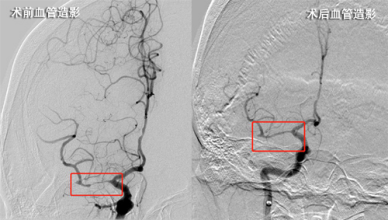

因患者错过最佳药物溶栓时间窗,与家属协商后,卒中团队立即为该患者行急诊全脑造影备支架机械取栓术。术中发现患者右侧大脑中动脉存在长节段极重度狭窄、前向血流缓慢,卒中团队讨论决定,采用血管内球囊成形术,必要时行支架植入术,尽快开通血管。经数十分钟努力,狭窄段血管开通成功,前向血流再通分级mTICI评分3级,提示血管再通成功。术中未使用支架植入,为患者省下数万元耗材费。

术后立即检查患者左侧偏瘫肢体,功能明显好转,术后几日患者肌力逐渐恢复正常,恢复生活自理能力。经过神经内科医护人员针对性诊疗和精心护理,患者的偏瘫和语言功能基本恢复正常,复查血管显示狭窄段血流通畅,现已痊愈出院。